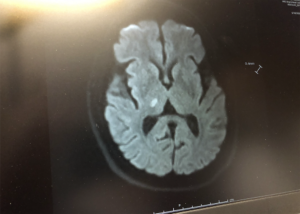

brain